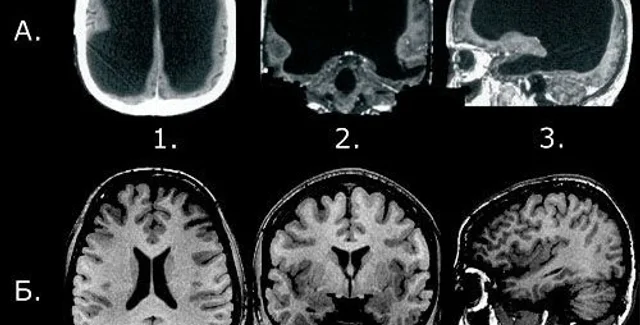

Платные анализы на сканирование мозга при помощи томографии становятся все более популярными среди здоровых людей, которые хотят развеять свои опасения по поводу риска диагноза рака мозга или инсульта.

Медики из университета Эдинбурга (Великобритания) рассмотрели почти 20 тысяч случаев сканирования мозга, проведенных по различным причинам. Среди людей, которым делали мозговую томографию, никто не имел никаких симптомов основных заболеваний мозга.

Неврологи зафиксировали, что даже при обнаружении случайных аномалий работы мозга в 3% случаев (таких как ослабленные кровеносные сосуды или доброкачественная опухоль) не существовало четких медицинских доказательств проведения лечения для таких пациентов.

По мнению ученых, такое отсутствие явных доказательств и показаний для конкретного лечения может ввести пациентов в заблуждение и даже привести к ненужным операциям. Основная трудность подобных медицинских осмотров заключается в неопределенности дальнейших действий для пациента с выявленной дисфункцией мозга.

Исследователи считают, что во избежание неправильных заключений люди должны проходить сканирование головного мозга только при наличии конкретных медицинских рекомендаций или уже установленного диагноза.